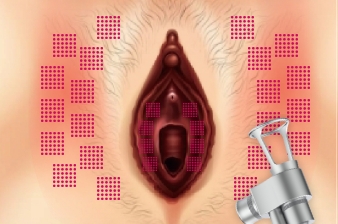

Vaginal remodeling and vulval tone improvement to raise the quality of women life.

Thermal stimulation of entire vaginal wall layer

Immediately after treatment, shrinkage of the vaginal skin fibers occurs. In addition, collagen growth is promoted and the vaginal wall becomes resilient and thick. Changed Vaginal structure after treatments makes its whole conditions better.

Effect of Laser Treatment Collagen Stimulation

- Vaginal Remodeling

- Vaginal Dryness

- Sexual Dissatisfaction

- Pelvic Organ Prolapse

- Urinary Incontinence

Bacteria Reduction

Vaginitis

Cunnus Pruitus

leucorrhea

It makes the same distance between tissue with laser so it guaranty the uniform laser irradiation into tissue to guaranty overall good vaginal tightening result.

Improve Vulva Discoloration